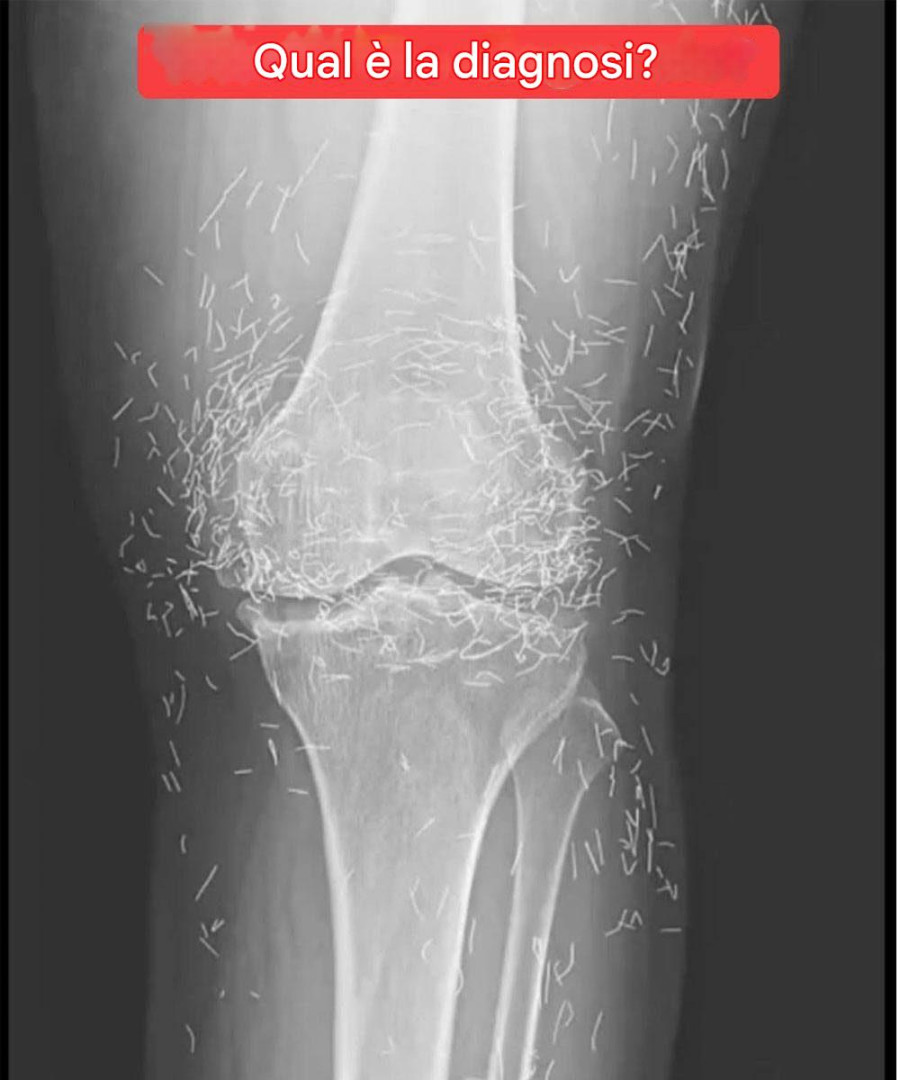

Una radiografia rivela centinaia di aghi d’oro nelle ginocchia di una donna

Mentre i medici esaminavano una radiografia delle ginocchia di un’anziana donna con forti dolori articolari, hanno trovato una miniera d’oro: centinaia di minuscoli aghi d’oro per agopuntura rimasti nei suoi tessuti.

Nel trattamento di agopuntura della donna, gli aghi, presumibilmente d’oro, sono stati lasciati intenzionalmente nei suoi tessuti per una stimolazione continua, afferma il rapporto.

Potrebbero anche rendere difficile la lettura di una radiografia da parte di un medico. “Gli aghi potrebbero oscurare parte dell’anatomia”, ha affermato Guermazi.